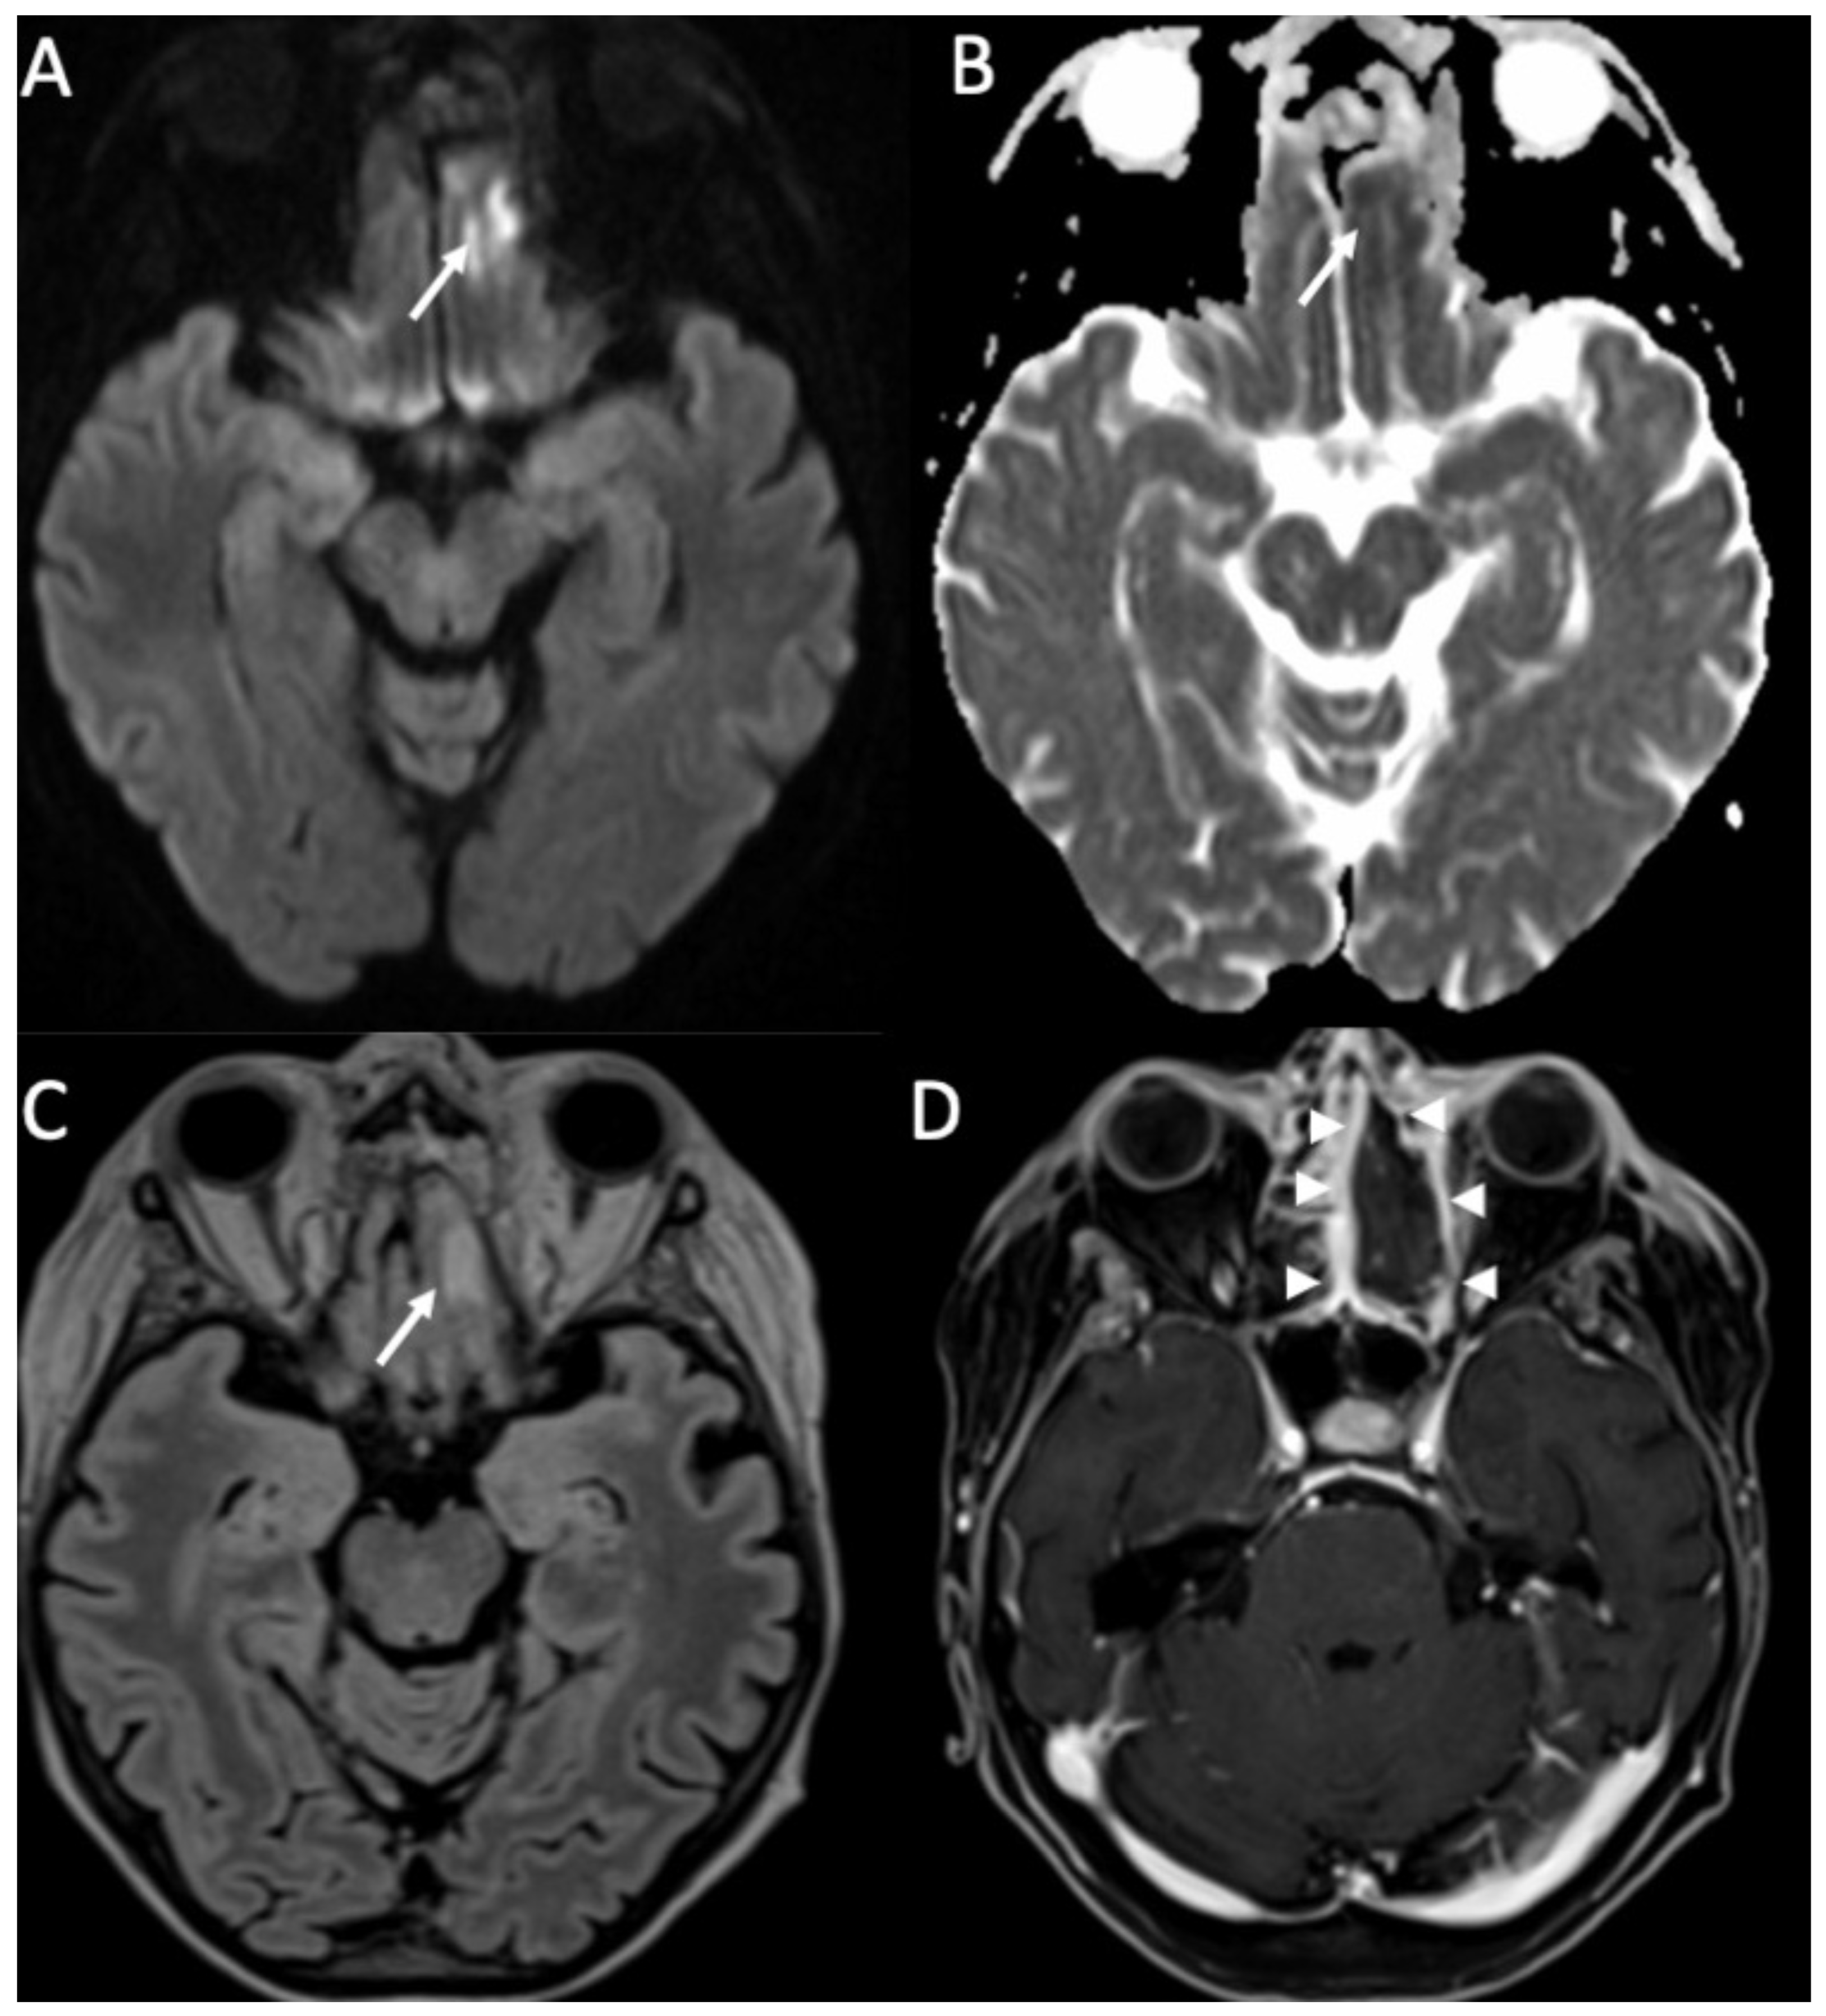

| Tuberculosis | • Leptomeningeal enhancement in the basal cisterns • Hydrocephalus very common • Infarcts in the basal ganglia due to vasculitis • Possible concomitant tuberculomas or miliary tuberculosis |

3. Tuberculous Meningitis/Meningoencephalitis